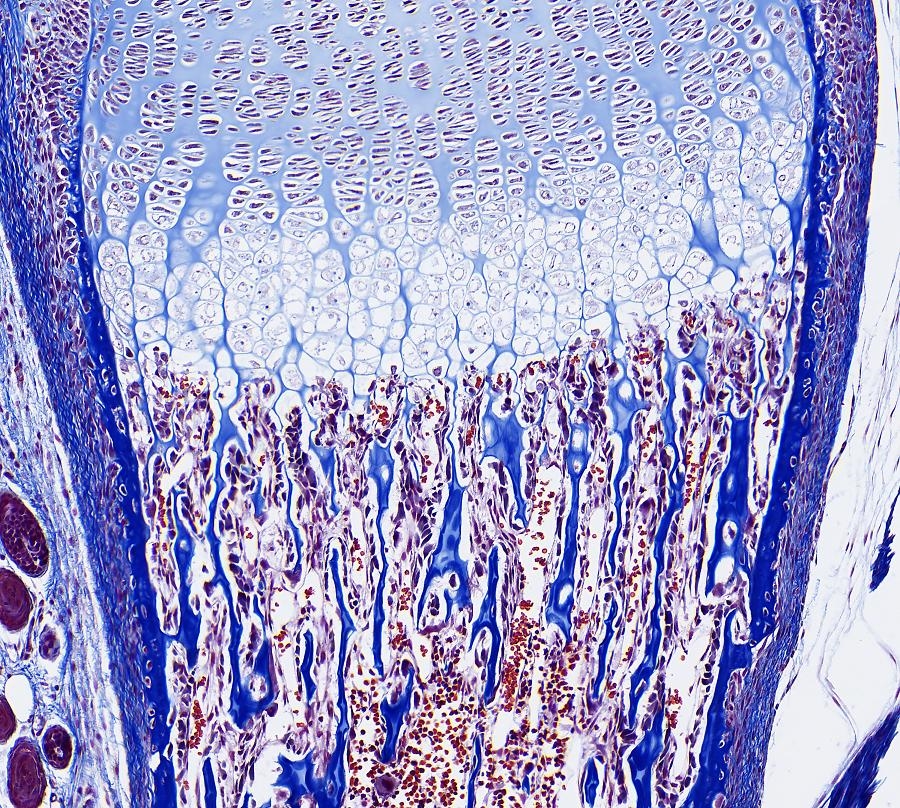

Chondrale Ossifikation,

Das Besondere der chondralen Knochenbildung ist, dass das zukünftige Skelettelement zuerst knorpelig angelegt wird. Dieses Knorpelstuck wird dann in einem komplexen Prozess abgebaut und durch Knochengewebe ersetzt (indirekte Knochenbildung). Durch dies en Mechanismus entstehen die meisten Knochen des Körpers, z. B. die Extremitätenknochen und die Wirbel.

Knorpel-Knochen-Grenze Im wachsenden verknöchernden Skelettstück lasst die Knorpel-Knochen-Grenze einen regelhaften Aufbau erkennen.

• Der Knorpel der (noch) nicht verknöcherten Epiphyse ist fetaler Knorpel.

• In Richtung auf die Verknöcherungszone folgt dann der Säulenknorpel, in dem die Knorpelzellen proliferieren und sich in Reihen (Säulen) anordnen; diese Knorpelzellen sind oft etwas abgeflacht.

• Es folgt dann die Zone des Blasenknorpels mit seinen großen mitochondrienreichen ("hypertrophen") Zellen, in deren Umgebung die Knorpelmatrix verkalkt.

• Es folgt die Eröffnungszone, die Front zur Zone der Knochenbildung, an der die Knorpelzellen abgebaut und die Knorpelhohlen sowie die spießartig dazwischenliegende verkalkte Knorpelmatrix von Osteoblasten besiedelt werden, die mit der Abscheidung von Knochenmatrix beginnen.

• Der Eröffnungszone, in der auch die meisten Chondroklasten zu finden sind, schließt sich dann die sehr gefaßreiche Zone mit Knochenbälkchen an, die hier oft noch Reste verkalkter Knorpelmatrix enthalten und an denen auch schon Osteoklasten auftreten, als Zeichen für schon sofort beginnende Umbauvorgange.

Knorpel = Leichtblau;

Knochen = Dunkelblau;

Stitch von 3 Bilder mit ein 25x Plan Fluotar Objektiv.